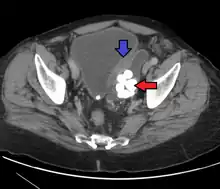

Bladder diverticula containing stones. The bladder wall is thickened due to possible transitional cell carcinoma.